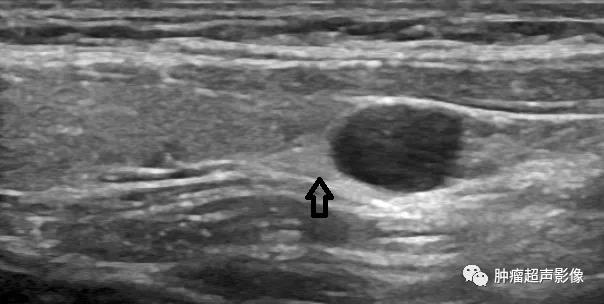

甲状旁腺囊肿的发生率较低,病因尚不完全清楚,可发生于下颌骨至上纵隔的颈前各区域,根据其生化指标及临床表现,可分为功能性和无功能性,其中无功能性的约占总数的80%左...